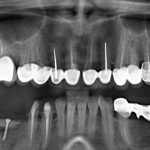

Например, в следующей ситуации:

Оставить так, как есть — это значит, сильно рисковать имплантом и объемом альвеолярного гребня — фактически, большая часть импланта пятого зуба «висит в воздухе». Поэтому получившуюся костную полость мы заполняем аутокостной стружкой в смеси с Bioss и закрываем коллагеновой мембраной BioGide: